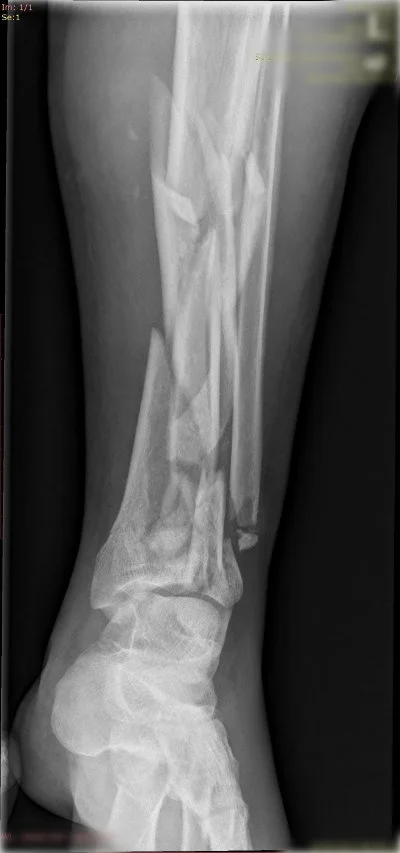

Görüntüleri büyütmek için resmin üstüne tıklayınız.